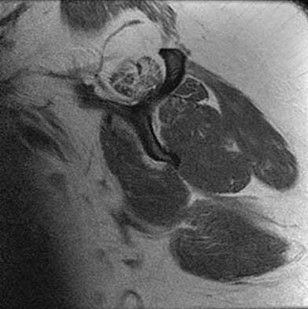

Tarsal coalitions occur when primitive mesenchymal cells fail to differentiate and form the

normal articular separations between the tarsal bones of the hindfoot. Overall incidence is difficult to determine because many affected people are minimally symptomatic or asymptomatic. Symptomatic tarsal coalitions typically present in adolescents as a painful flatfoot; however, there are a number of possible presentations, and occasionally symptoms do not appear until adulthood. Most tarsal coalitions are between the calcaneus and the navicular (CN) and the talus and the calcaneus (TC). Although most TC coalitions are across the middle facet, posterior facet coalitions do occur. Plain radiographic evaluation of suspected tarsal coalition is the mainstay for diagnosis. However, coalitions can be bony or fibrous, and making the diagnosis can be difficult. The addition of CT images to distinguish bony definition and MR images to decipher soft tissue can aid in diagnostics. Bony coalitions appear as definite bony bridging between the bones, while fibrous coalitions are suspected when distortion of the bony anatomy is seen. Bony coalitions are best seen on the oblique view (CN) and Harris axial view (TC). There are a number of secondary signs such as the anteater (AE) sign (elongation of the anterior process of the calcaneus as it extends to the navicular as seen on the lateral view [CN]). talar beaking (traction spur of the talar neck thought to result from abnormal stresses as seen on the lateral view [both CN and TN]), and the “C” sign (a continuous cortical contour from the medial talus to the sustentaculum tali [ST]) as seen on the lateral view (TC). A number of newer signs are not as well known, such as a broad mediolateral dimension of the navicular on the anteroposterior (AP) view (the

navicular is wider than the talar head [CN]), nonvisualization of the middle facet on the lateral view (TC), the brick sign (a normal ST is flat, but a distorted ST is enlarged and curved [CN]), and a tapered lateral navicular bone as seen on the AP view (the medial navicular [CN] is much thicker than the lateral navicular).

Figure 3a shows a flatfoot. Figure 3b shows an MF and TB, but not a C sign. Figure 3c shows a bony irregularity between the calcaneus and the navicular and a WN. Figure 3d shows an MF. Figure 3e shows an MF, but narrowing or loss of the posterior facet. Figures 3f through 3h show medial edema and joint irregularities consistent with a posterior facet coalition.